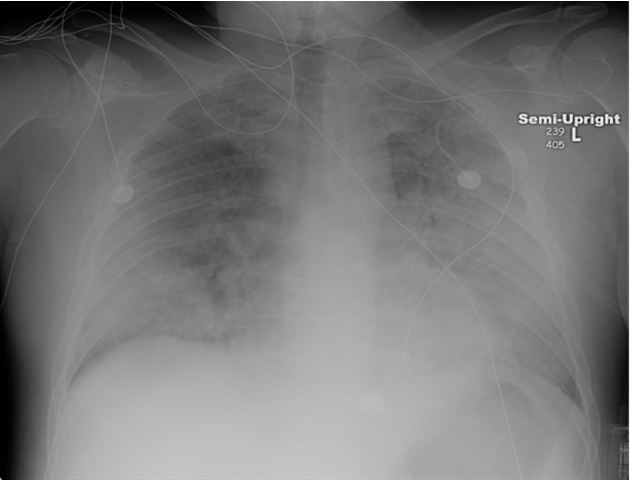

The patient was treated for sepsis and severe community acquired pneumonia with empiric piperacillin- tazobactam and vancomycin. Over the next two days, the patient’s respiratory status worsened and he required intubation and mechanical ventilation. Chest radiographs showed bilateral diffuse pulmonary infiltrates consistent with acute respiratory distress syndrome (ARDS) (Figure 2). Bronchoscopy with bronchoalveolar lavage revealed no evidence of alveolar hemorrhage, cell count with 65% neutrophils, 26% lymphocytes and 9% macrophages and cytology and all cultures were unrevealing. HIV serology was negative. Legionella urinary antigen was negative. The subsequent physical examination showed a petechial rash on the lower extremities.

Figure 2: Chest radiograph in the Intensive Care Unit